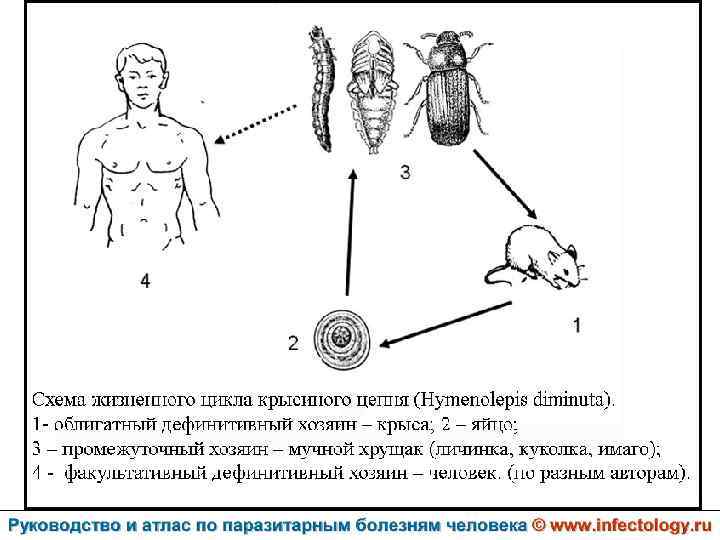

Гименолепидоз крысиный (диминутный) (шифр по МКБ 10 – B 71. 0) – зоонозный гельминтоз, для которого человек является случайным хозяином. Характеризуется нарушением деятельности пищеварительной и нервной систем.